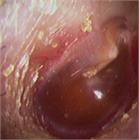

1. 扁桃肥大(アデノイド肥大を含む)は小児の睡眠時無呼吸(obstructive sleep apnea:OSA)を含む閉塞性睡眠時呼吸障害(obstructive sleep-disordered breathing:oSDB)の最も一般的な原因であり、このような小児患者に口蓋扁桃摘出術 ± アデノイド切除術は非常に有効である。一方、扁桃肥大は成長とともに軽減すること、術後出血などの術後合併症もみられることから、手術適応は慎重に評価しなければならない。成人の扁桃肥大では腫瘍性病変の可能性を念頭に置いて診断を進める必要がある。